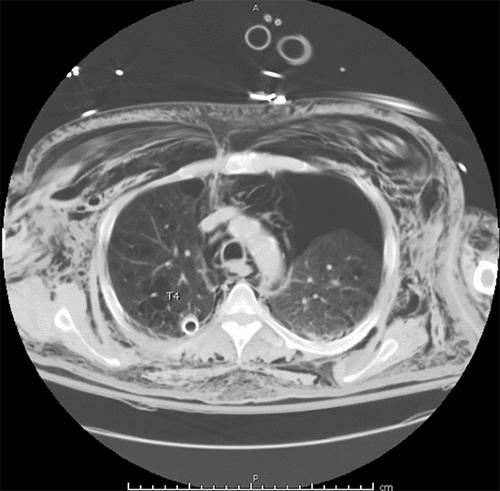

Additionally, the CTA chest confirmed acute displaced fractures of the posterior right 7-10th ribs and nondisplaced fractures of the right 11th and 12th ribs. A moderate to large left-sided pneumothorax was also revealed (Figure 2), and a second chest tube was placed. No facial fractures were identified on imaging.

Figure 2. CT Chest Scan Demonstrating Large Left Pneumothorax. Published with Permission